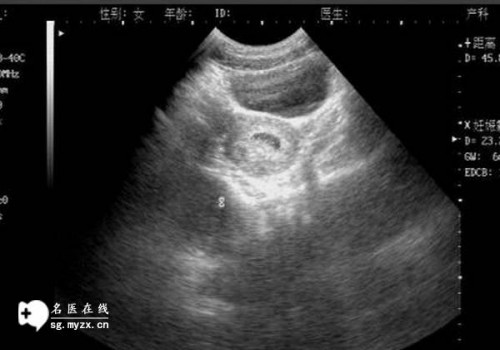

輸卵管堵塞是一種關(guān)于生殖健康的常見(jiàn)問(wèn)題,因?yàn)樗赡苡绊懙缴芰?。輸卵管堵塞可能?huì)導(dǎo)致不孕不育。因此了解輸卵管堵塞的原因和預(yù)防措施,以及如何處理它們,是非常重要的。

輸卵管堵塞的原因可以分為內(nèi)部原因和外部原因。內(nèi)部原因是指輸卵管的結(jié)構(gòu)本身導(dǎo)致的,比如輸卵管的萎縮、內(nèi)膜發(fā)育不良、輸卵管結(jié)石等,都可能導(dǎo)致輸卵管堵塞。外部原因一般是指外部因素導(dǎo)致的,比如宮外孕、宮腔粘連、外傷等,這些都可能會(huì)導(dǎo)致輸卵管堵塞。

輸卵管堵塞的癥狀一般比較模糊,常見(jiàn)的癥狀有疼痛、反復(fù)發(fā)熱、反復(fù)腹痛和經(jīng)期不規(guī)律等,這些癥狀可能會(huì)讓人感到困擾。

當(dāng)發(fā)現(xiàn)輸卵管堵塞時(shí),應(yīng)及早就醫(yī),并根據(jù)病情選擇適當(dāng)?shù)闹委煼椒āMǔG闆r下,醫(yī)生會(huì)根據(jù)患者的具體情況,采用手術(shù)、藥物或血液療法來(lái)治療輸卵管堵塞。有時(shí)醫(yī)生會(huì)采用體外受精的方法來(lái)解決輸卵管堵塞問(wèn)題,以便讓患者成功懷孕。